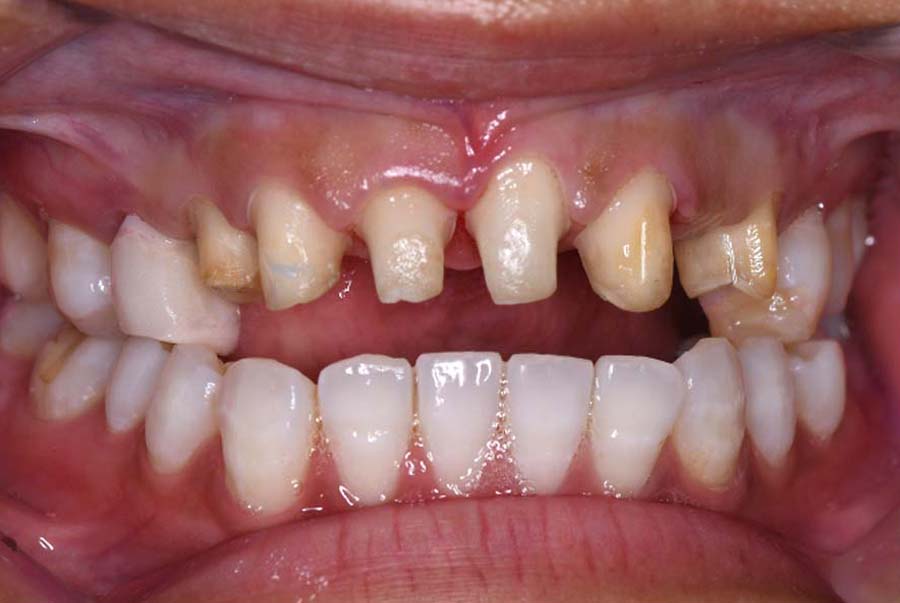

| 治療内容 | ①スプリントを装着 ②副子を装着 ③2024年4月 口腔内反映開始 ④副子を入れた状態の所まで咬合を挙上 (バイトアップ) ⑤2024年5月 上顎前歯部8本に仮歯(TEK) を装着 |

初診日 2023年10月12日